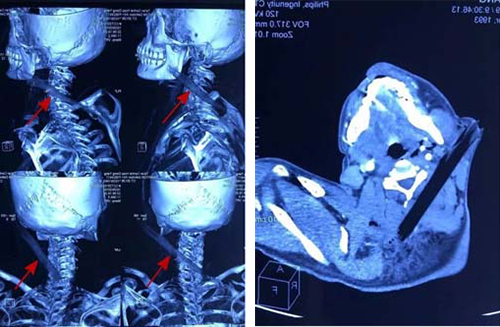

医院耳鼻咽喉头颈外科急诊医师接诊后,迅速检查患者伤情,检查示患者意识可,无呼吸困难、肢体活动障碍、肢体感觉异常,右颈部自耳垂下方插入颈部一不规则木枝样物,颈部无活动性出血,头皮部、胸部多发创伤。急诊医师阅读外院颅脑、颈部、胸部CT示颈部异物自右颈向后下越过脊椎后方至左颈部、颈部血肿、颈部皮下气肿、头皮下血肿、胸骨骨折、上胸部皮下积气、纵膈血肿、创伤性湿肺,请神经外科、血管外科、创伤急诊外科急会诊,认为目前患者无明确颅内出血、脊髓损伤指征,异物与颈部大血管关系不明确,建议行颈部CTA。患者完善颈部CTA显示异物紧靠颈内动脉,必须立即手术。

耳鼻咽喉头颈外科许风雷主任医师带领团队,在第二麻醉手术科保驾护航下进行急症手术,术中见异物自右颈部插入,经过胸锁乳突肌内侧面,紧靠颈内动脉插入颈后部。树枝表面不光滑,与周围解剖关系复杂,术中仔细分离,取出异物,是一根不规则长柱形木棍,长约15cm手术顺利完成,患者术后很快苏醒,肢体活动正常,颈部活动良好。